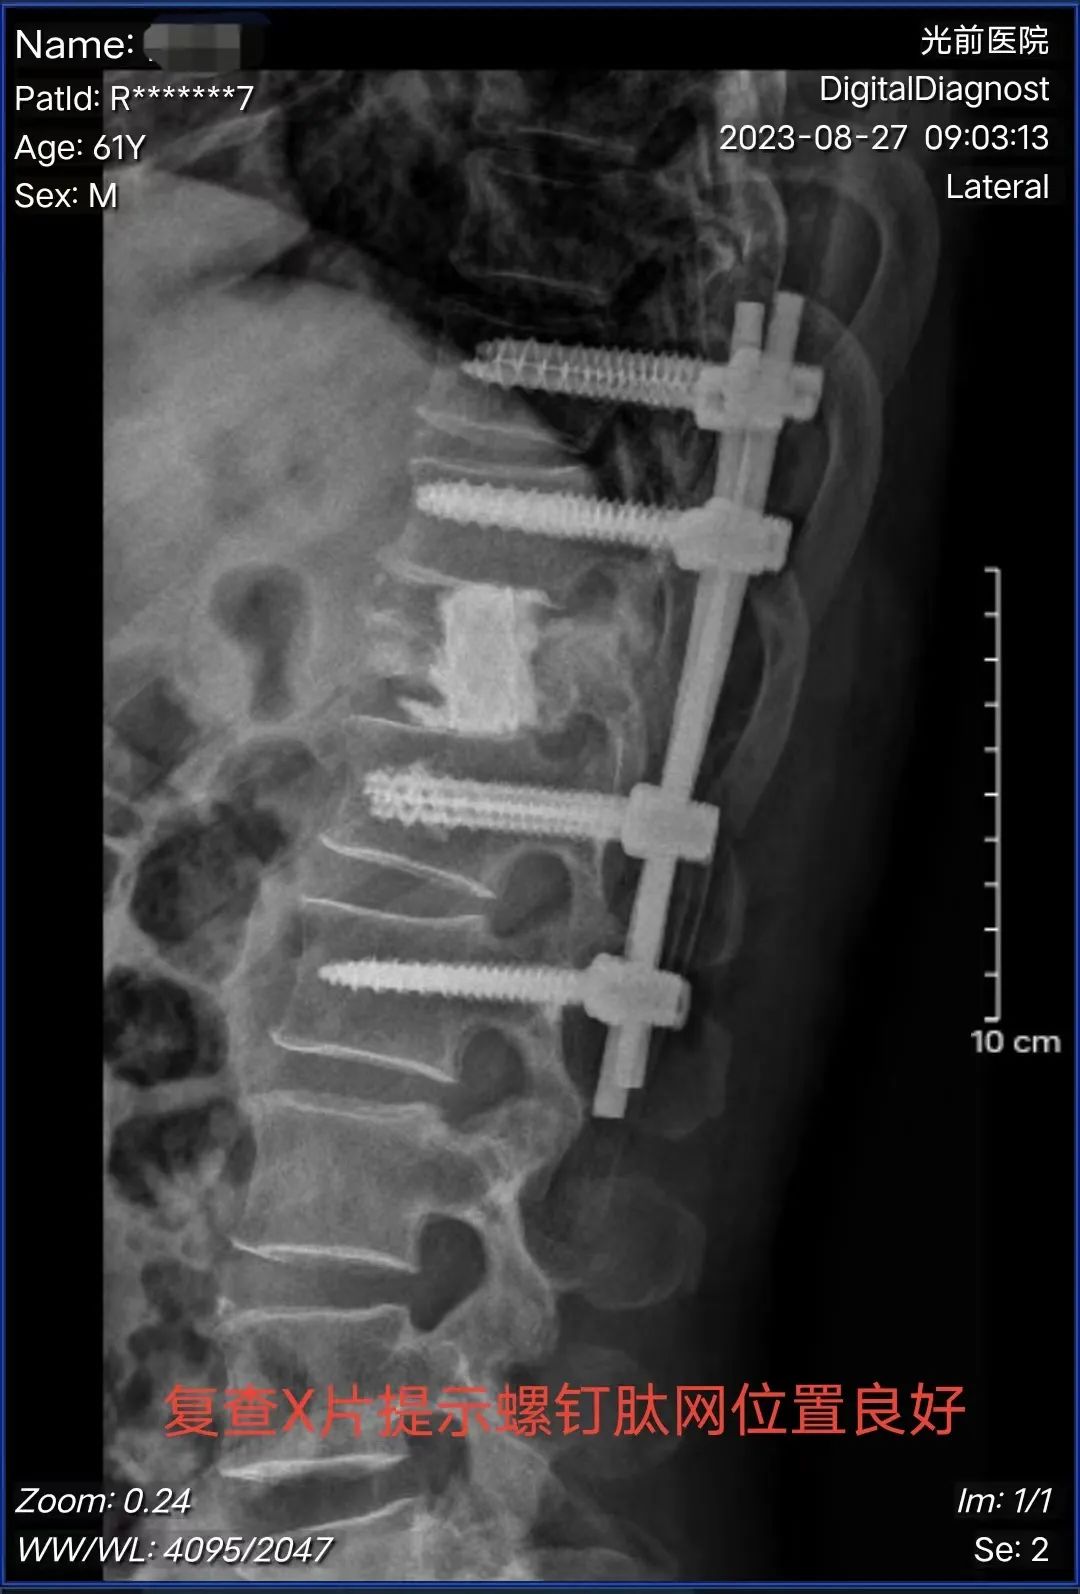

黃進(jìn)福主任帶領(lǐng)骨科團(tuán)隊(duì),結(jié)合陳阿伯腫瘤病灶侵犯的情況,對其病情進(jìn)行認(rèn)真研究,陳阿伯左下肢肌力0級,右下肢肌力2級,肛門括約肌反射差,決定行“后外側(cè)入路下胸12椎體部分切除+鈦網(wǎng)植入+骨水泥填塞+椎弓根釘內(nèi)固定術(shù)”。

術(shù)中,患者病情復(fù)雜,腫瘤病灶疤痕粘連厲害,容易出血,黃主任憑借扎實(shí)的解剖知識(shí)、豐富的手術(shù)經(jīng)驗(yàn),以及團(tuán)隊(duì)的默契配合,順利分離出神經(jīng)根,顯露胸12椎體,將病灶切除后,植入鈦網(wǎng)支撐椎體高度,并打入骨水泥填塞間隙,最后椎弓根釘固定,手術(shù)歷時(shí)3小時(shí),出血量300毫升。

▲手術(shù)前后影像對比

術(shù)后陳阿伯的左下肢束縛感得到明顯緩解。第二天,左下肢肌力恢復(fù)到2-3級,右下肢肌力3級,傷口干燥,恢復(fù)良好。